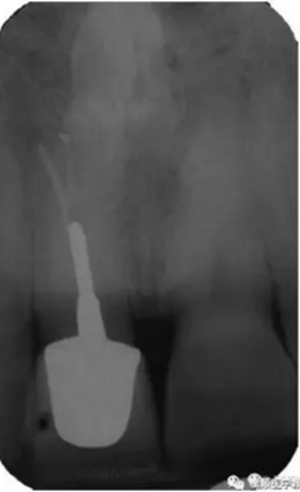

基于臨床檢查和X線片顯示,診斷為右上頜中切牙根尖周炎伴額外牙。治療計劃是先行患牙的根管治療,制作臨時義齒,最后制作樁核冠。應用橡皮樟和顯微根管技術,利用ProTaper旋轉銼配合使用 Hedstrom 銼和桉葉油,將根管內充填物取出,觀察X線片可見根尖三分之一處主根管一分為二,確定另一根管的工作長度,兩根管同行常規(guī)根管治療,充填后X線片顯示根管充填良好。樁核冠修復1年后,患牙無疼痛,影像檢查發(fā)現根尖顯影正常,根尖疾病治愈。

圖3. 樁核冠修復1年后患牙根尖周顯影